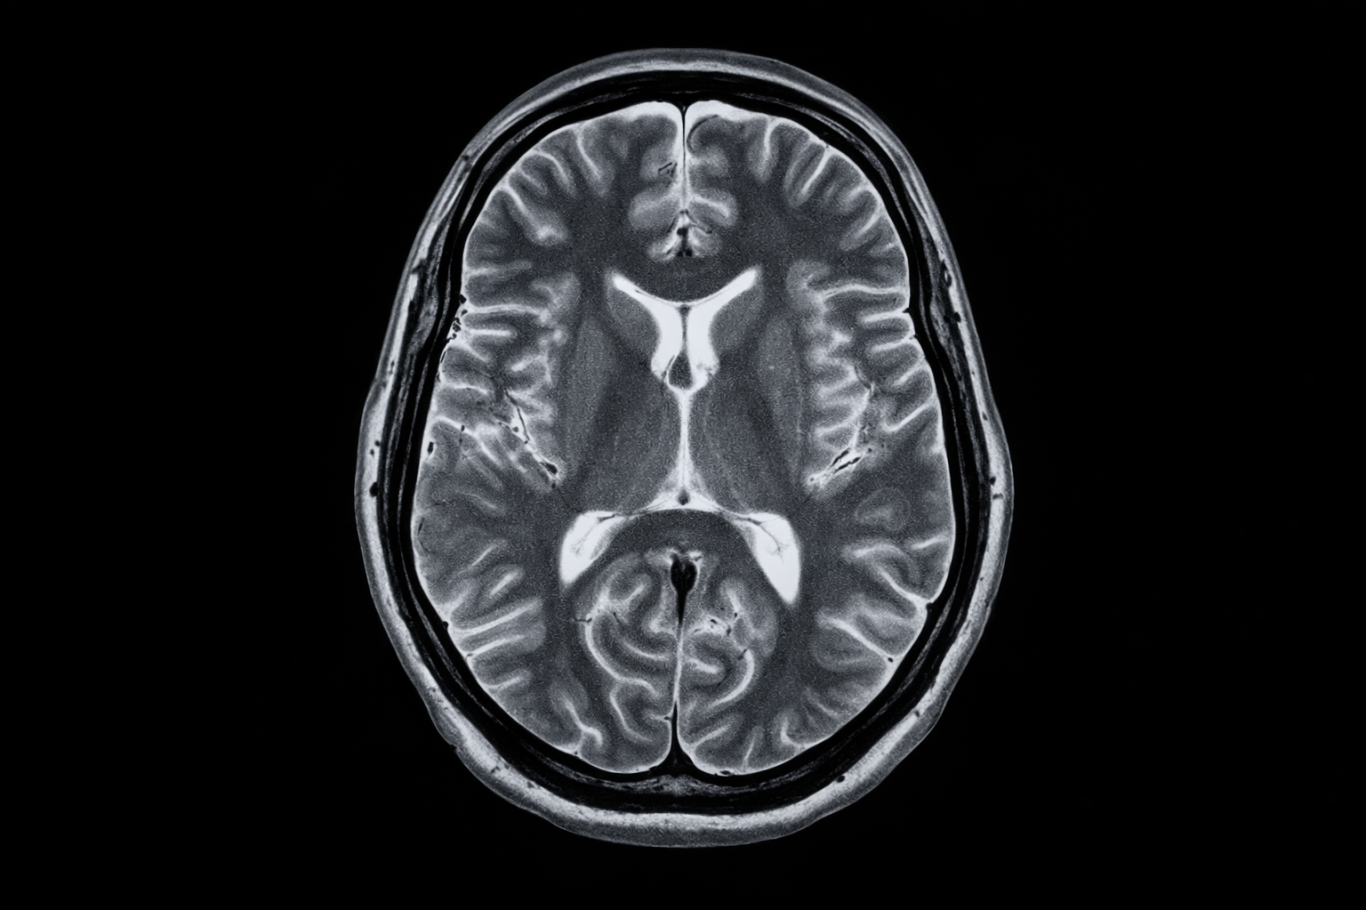

IRM

L’IRM (Imagerie par Résonance Magnétique) est un examen d’imagerie qui utilise un champ magnétique et des ondes radio pour obtenir des images très détaillées des organes et des tissus du corps. Elle est particulièrement utile pour l’exploration du cerveau, de la colonne vertébrale, des articulations et de certains organes. Cet examen ne comporte pas d’irradiation.